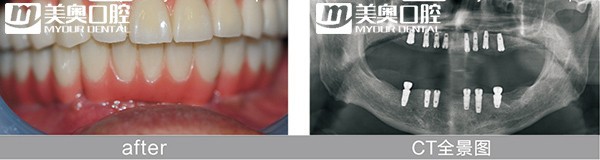

就在上个月,全口缺牙的63岁的徐先生在美奥口腔当天种牙,通过即拔即种即刻修复技术,拔除了2颗残根,同时种上种植体,安装牙冠,1天内就从缺牙到有牙;时隔一个星期,82岁的孟女士植人4颗植体,通过All-on-4即刻负重,当天戴上了整排牙,吃起了苹果;而上周末70岁的于先生因为需要种植6颗牙,计算了所有的费用,感觉有点负担,但因为购买了3个百元种牙福袋,获得了3颗免费的种植体,费用一下子减少了一半。

苏州美奥口腔院长王汉禹介绍,像徐先生这样的少量残冠无法保留的患者,他采用的是即拔即种,即刻负重的方式。在拔牙的同时植入植体,不必等待拔牙后3个月才种牙,植入种植体后也在当天就为他戴上了牙冠。

而像孟女士这样半口、全口的缺牙者,采取的是All-on-4即刻负重,半口缺牙只需在牙槽骨植入4颗植体,在当天戴上整排牙齿,恢复咀嚼力。将原本长达半年到1年的修复时期缩短到1天。不仅在戴牙当天可以吃饭,随着时间的推移,患者感到牙齿越来越有力。